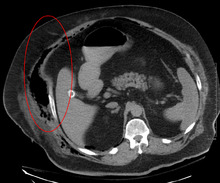

Necrotising fasciitis producing gas in the soft tissues as seen on CT scan

Early diagnosis is difficult as the disease often looks early on like a simple superficial skin infection.[4] While a number of laboratory and imaging modalities can raise the suspicion for necrotizing fasciitis, the gold standard for diagnosis is a surgical exploration in the setting of high suspicion. When in doubt, a small "keyhole" incision can be made into the affected tissue, and if a finger easily separates the tissue along the fascial plane, the diagnosis is confirmed and an extensive debridement should be performed.[2]

Computed tomography (CT scan) is able to detect about 80% of cases while MRI may pick up slightly more.[15]